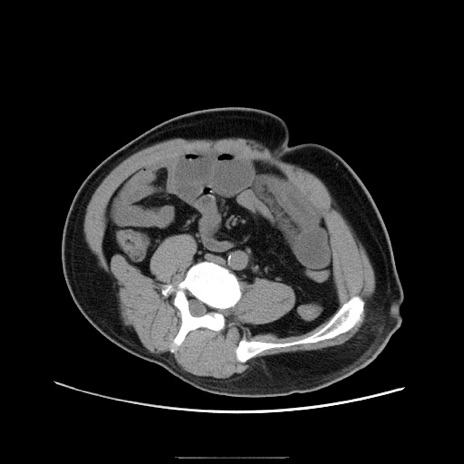

症例22(横断像)

【症例】50歳代男性

【主訴】腹痛

【現病歴】AVMからの被殻出血のため回復期リハ病棟入院中。 本日午後3時頃急に下腹部痛が出現した。

【既往歴】AVM、被殻出血、虫垂炎、高血圧

【身体所見】意識晴明、左半身不全麻痺、会話の理解は良好、36.5°C、腹部:膨隆、全体に板状硬、下腹部正中に圧痛点あり、反跳痛-、筋性防御不明、右下腹部にope scar

【データ】WBC 9400、CRP 0.06